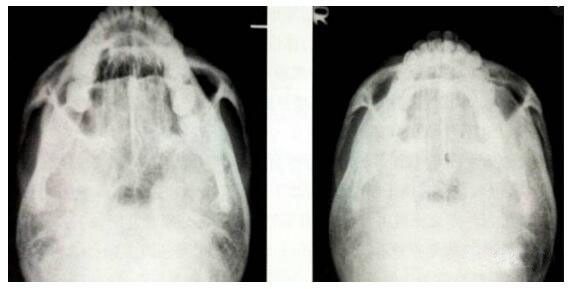

这个手术方法创伤比较小,恢复比较快。术后三个月内注意不要强力压迫颧弓处,手术果,X线片也显示颧弓内收的果显著▼

图 / 微创法颧弓内推手术的X线片术前、术后的果比较